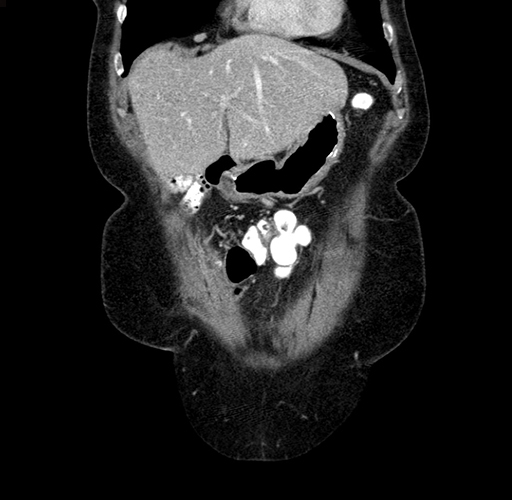

Pre-Chemo: Coronal Venous

Coronal Venous